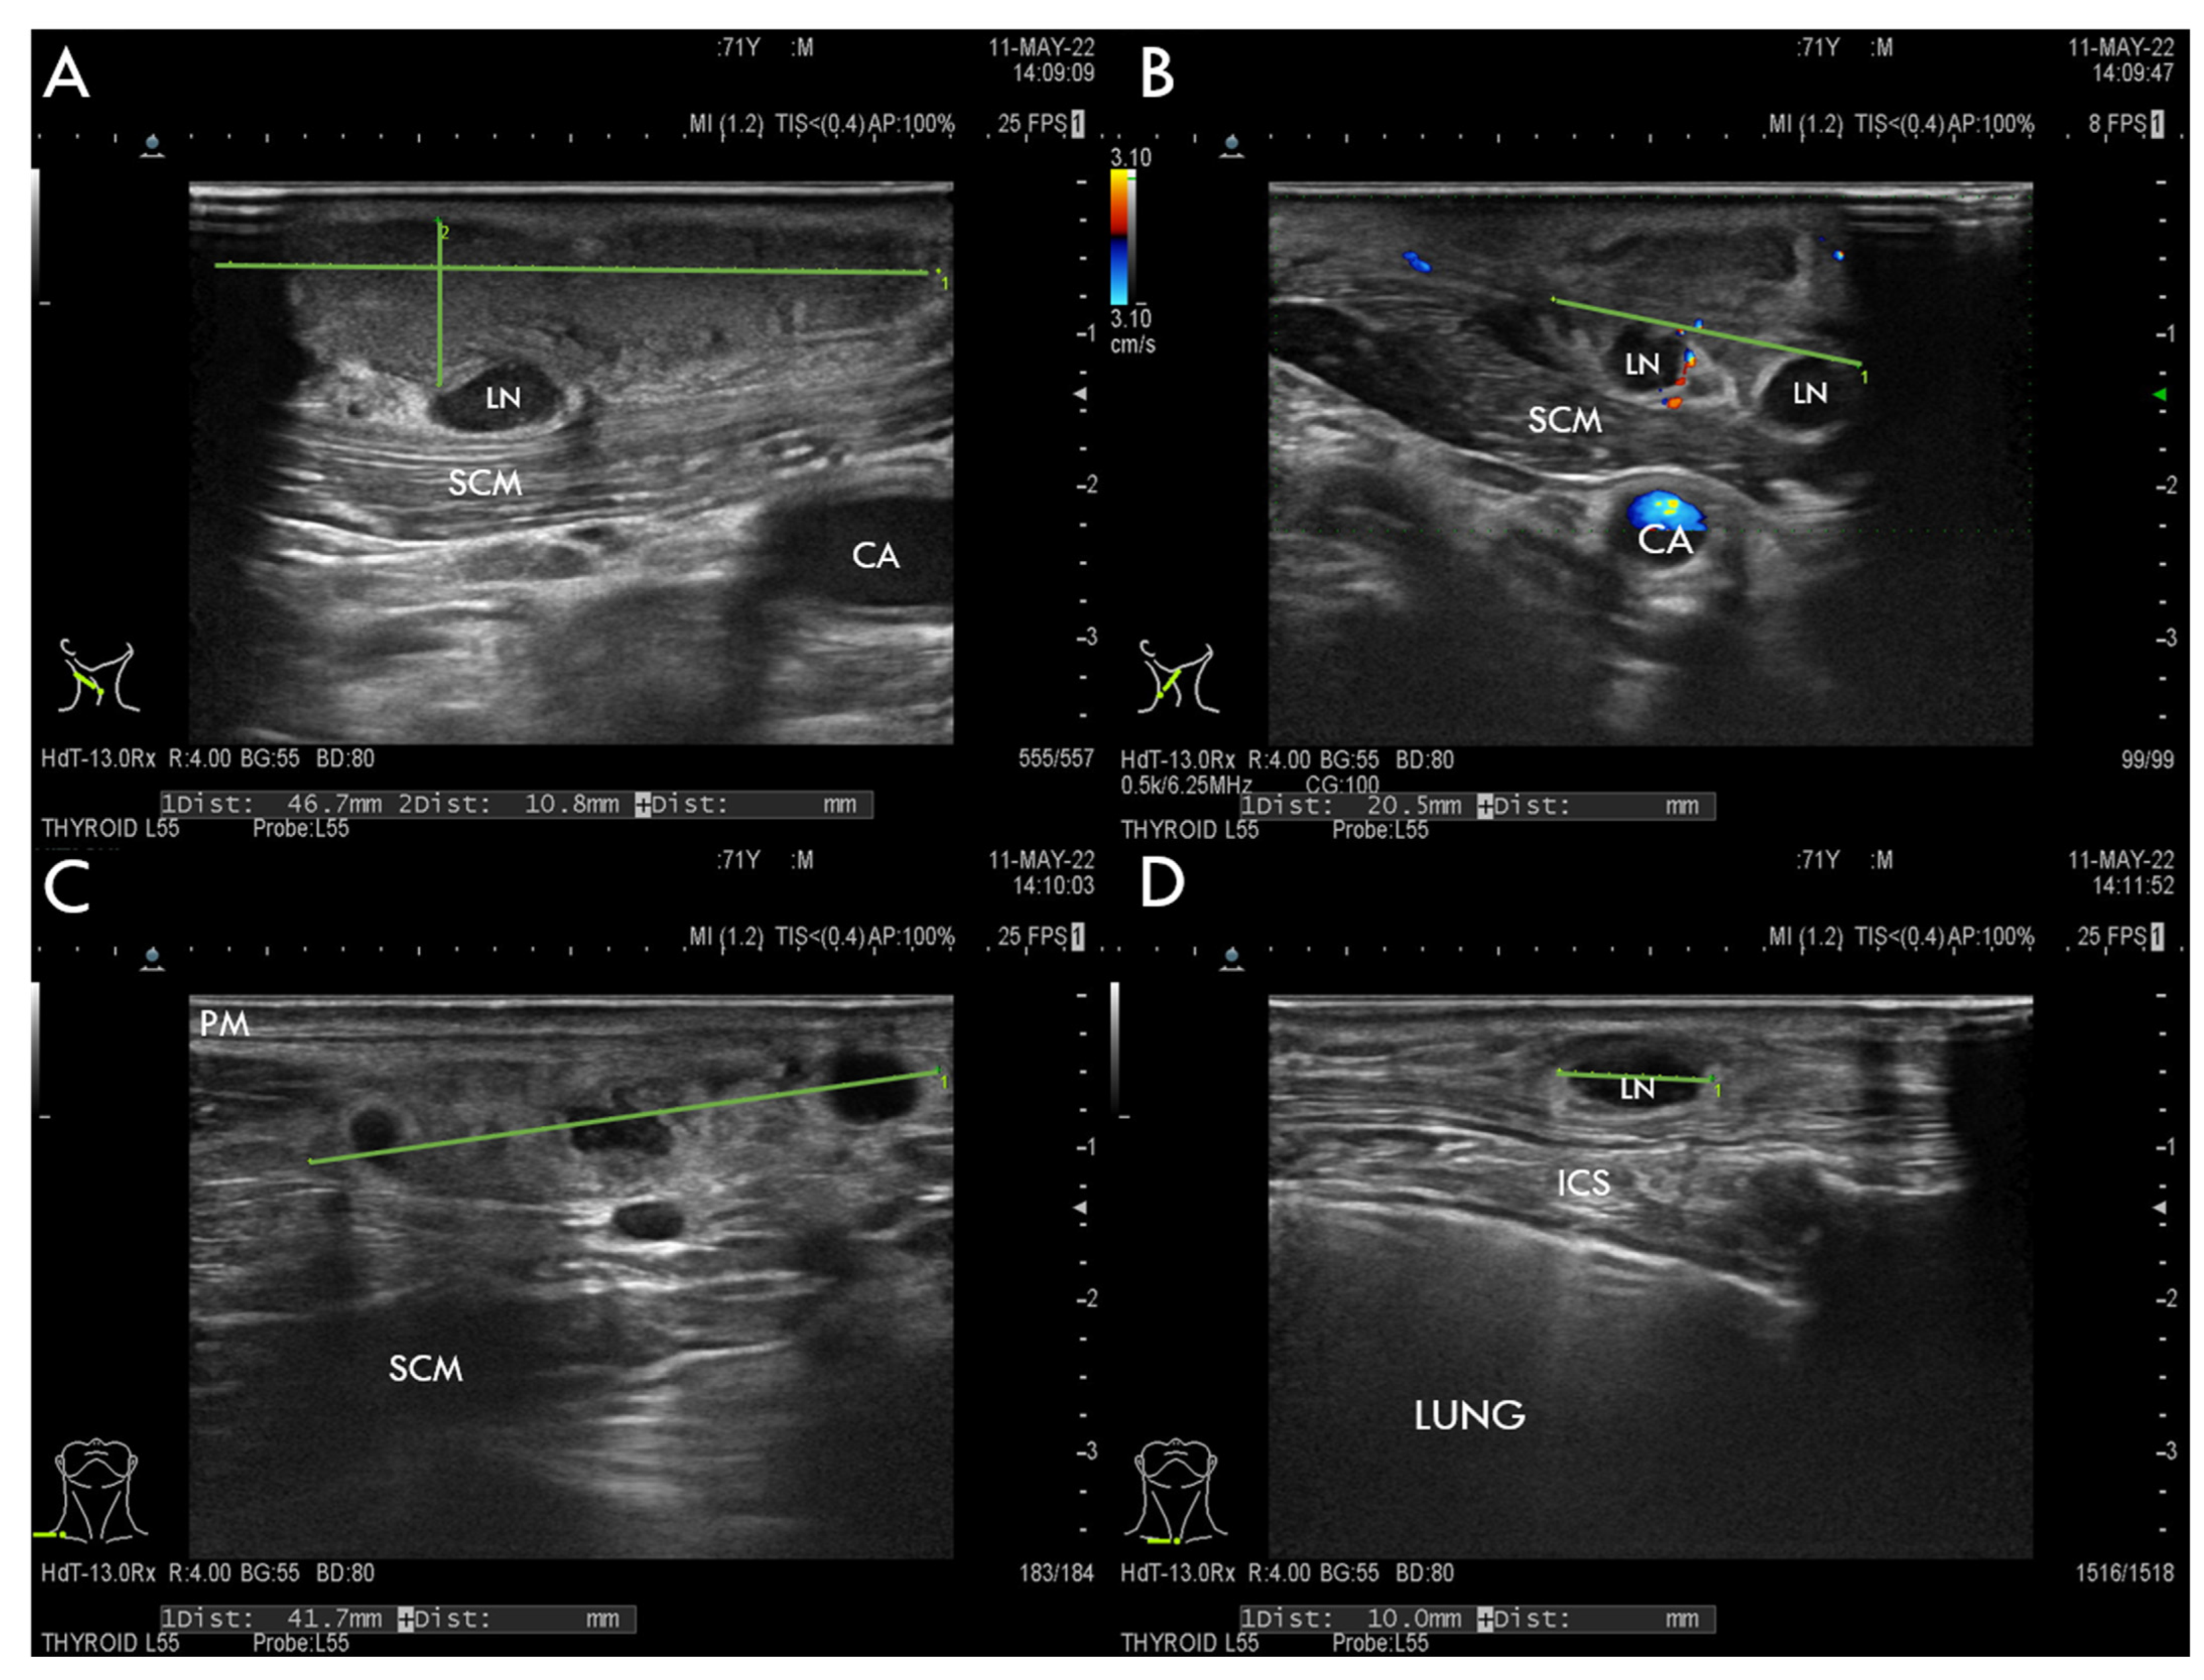

11.3. Imaging Studies